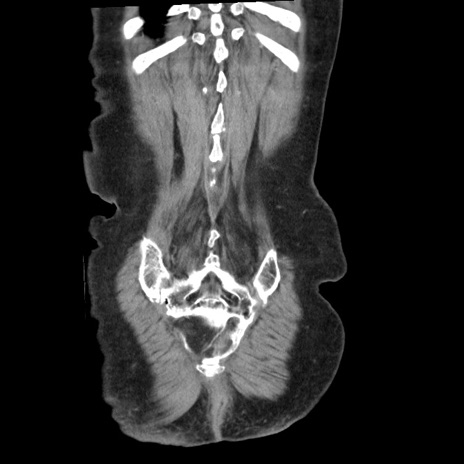

矢状断像